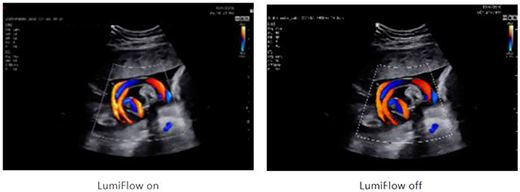

利器3:MV-Flow銳微成像、LumiFlow銳彩成像技術可非常靈敏顯示微小血管和超低速血流,清晰顯示胎兒顱內靜脈系統,配合對胎兒顱內竇匯(TH)的顯示可作為評估小腦幕位置改變的間接征象。